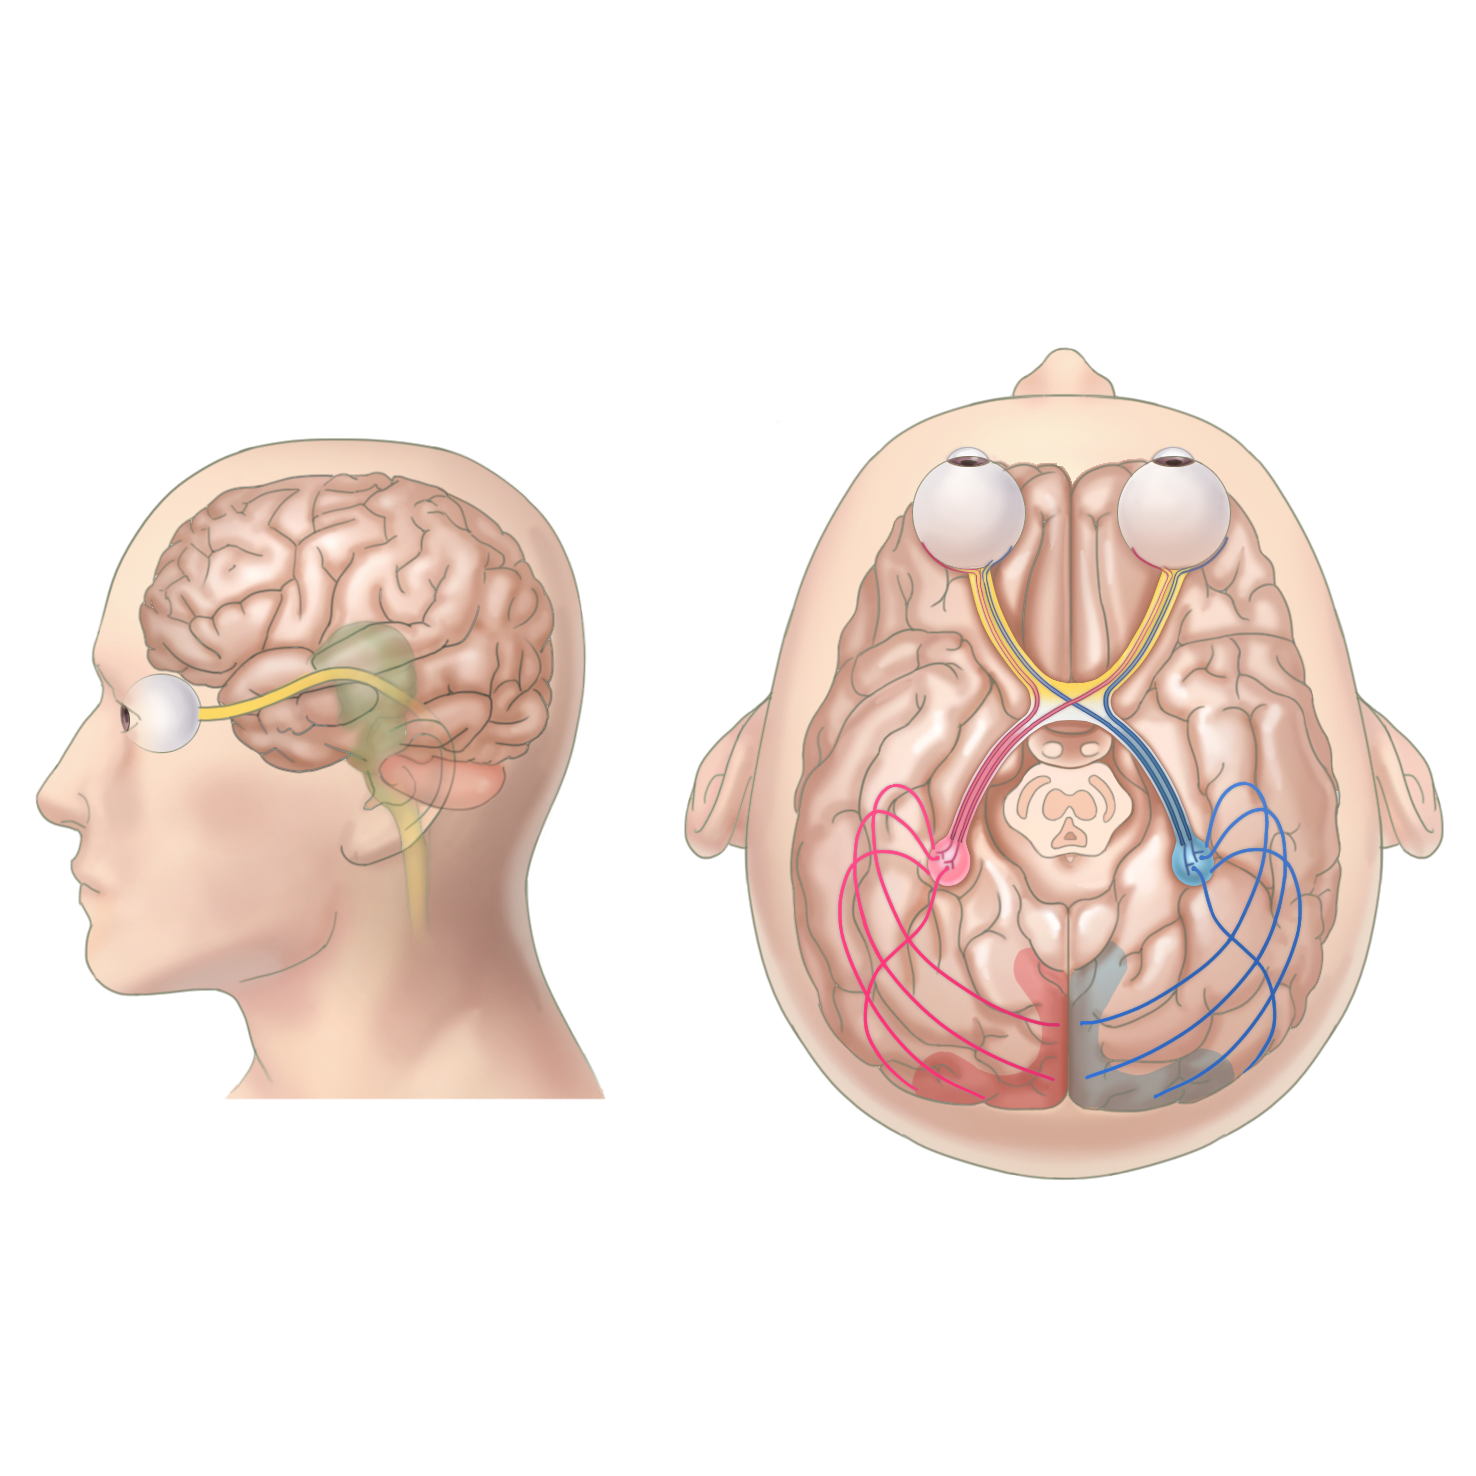

들어온 빛은 유리체를 통과해서 최종 망막에 초점이 맞추어지며, 망막에 맺힌 이미지는 시신경을 통해 뇌로 전달되어 본 것을 인지하게 됩니다.